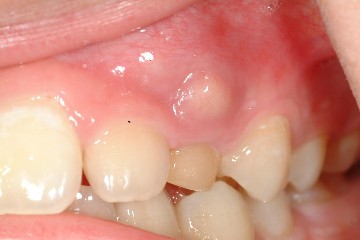

以下圖片分別為手術前、手術後情形

圖四 |